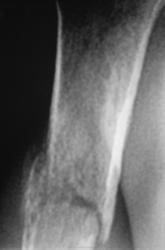

Случай 1

Случай 2.

Случай 3.

Случай 4.

Случай 5.

Нет. Просто сгорела трубка на диагностическом, и пол года были без рентгенодиагностического аппарата. Клепали на флюорографе и на передвижном.

А что, это выход. Мы на РЕНЕКСЕ с целью экономии пленки в голодные времена всегда делаем кости, суставы, ППН, черепа и даже пассаж бария по кишечнику. Шейный отдел смотрится великолепно, грудной - только у худых. ТБС и поясницы не делаем - боюсь спалить трубку. Запрещаю делать только травму, кисти (на артроз-артрит), стопы под нагрузкой, т.к. мелкие детали при увеличении "рассыпаются" и углы мерить не чем.